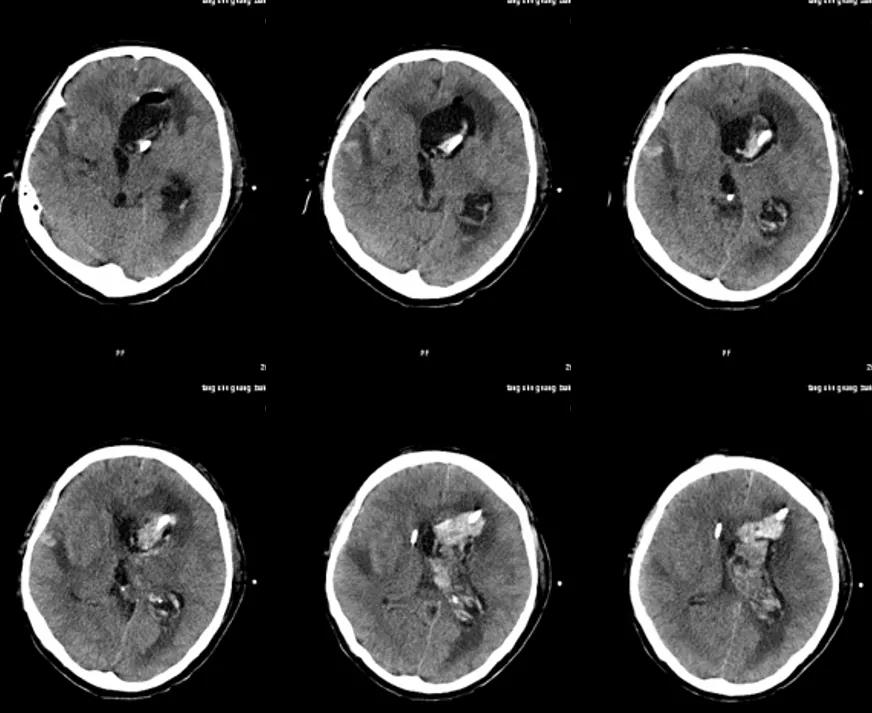

术中絮状物培养结果回报为:镰刀菌属(图13);病理提示符合真菌感染(图14)。

图13. 术中絮状物培养结果